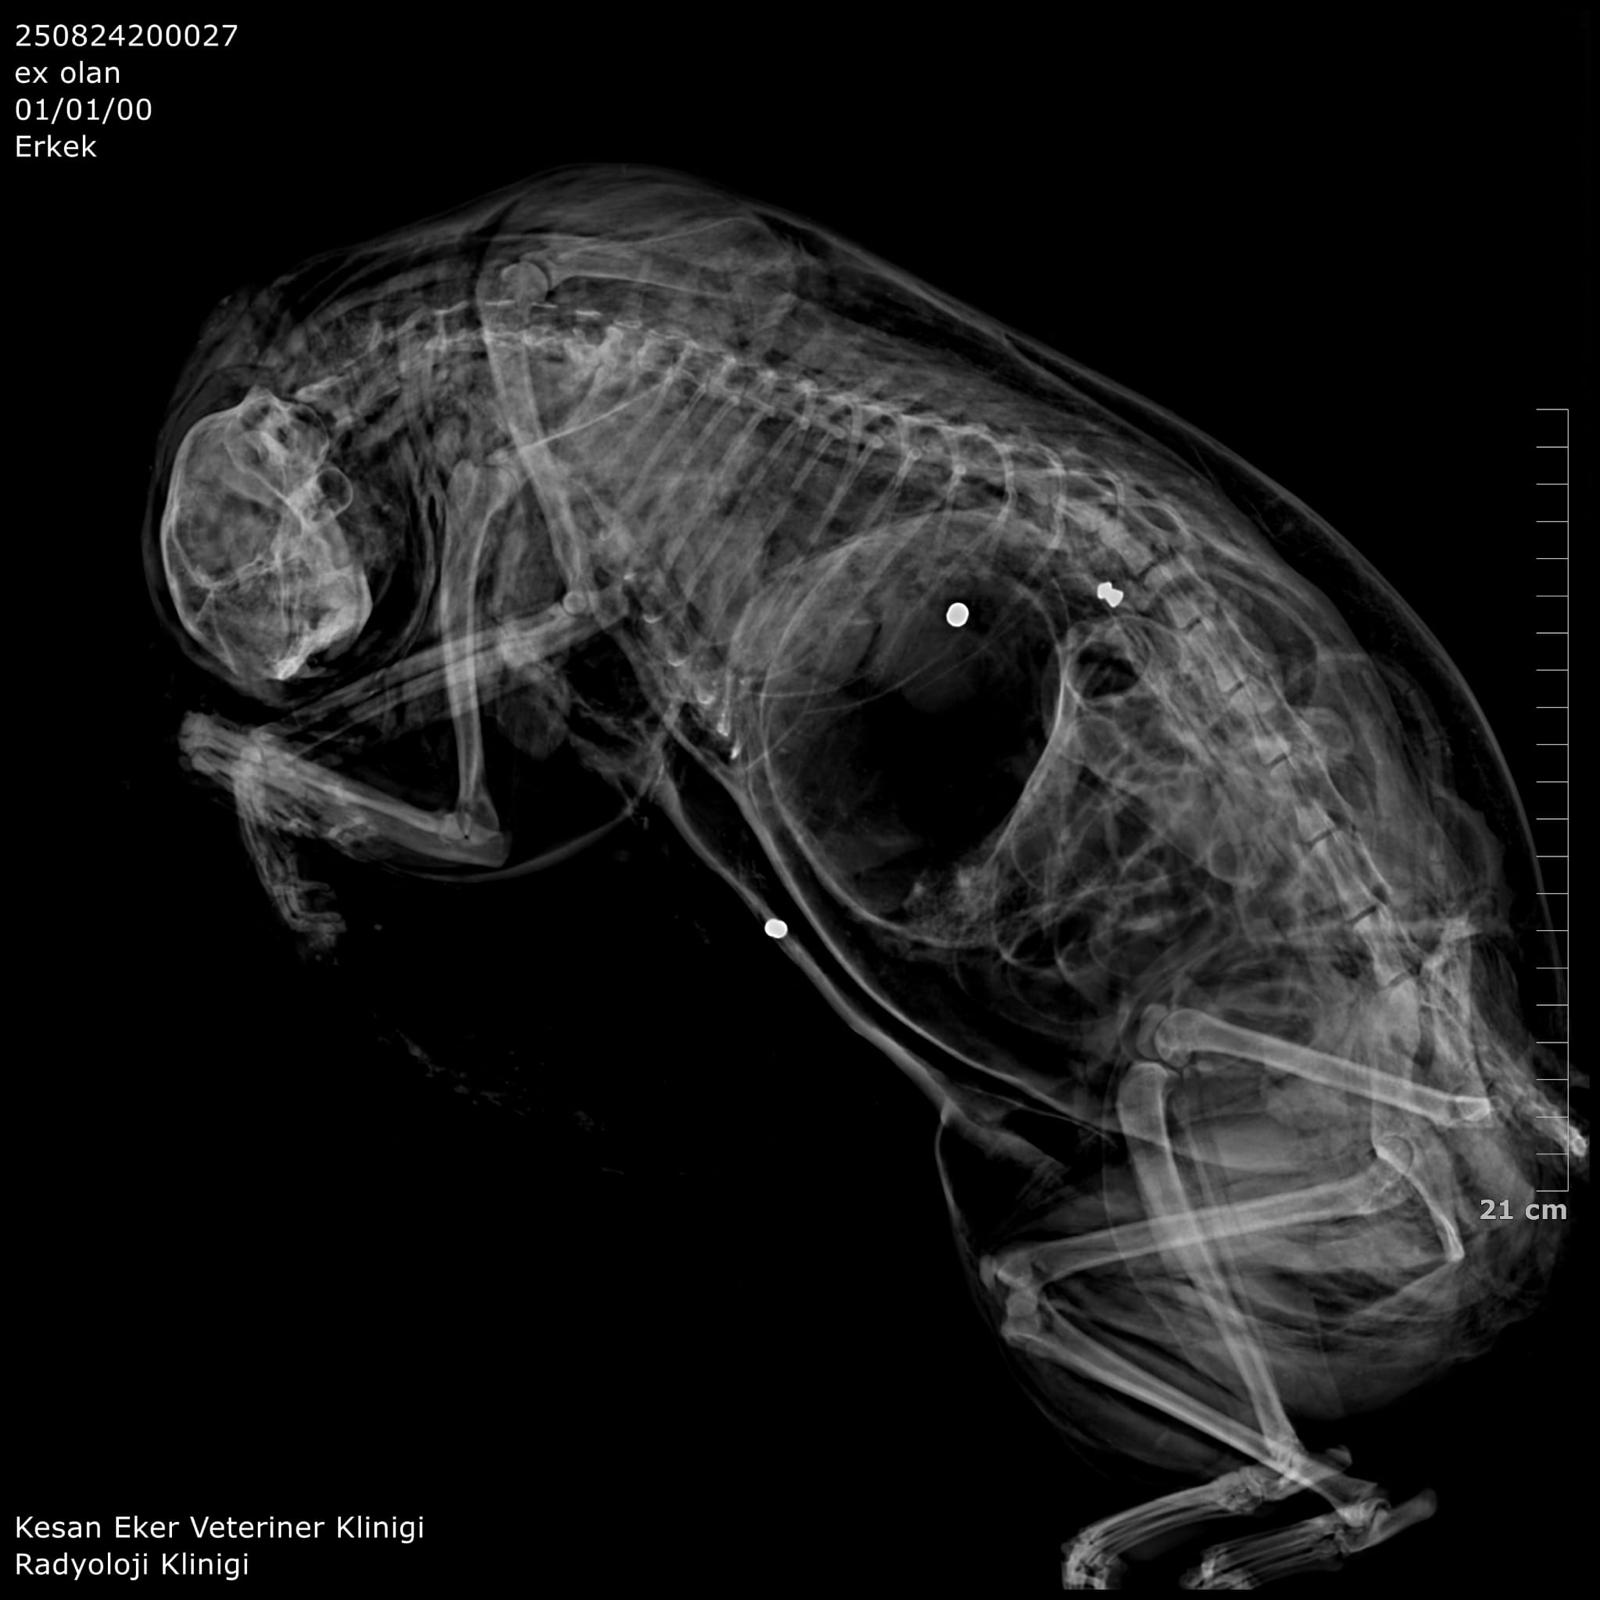

İpsala Cumhuriyet Başsavcılığı'nın olaya ilişkin hazırladığı iddianamede K.G., hakkında, 'Bir ev hayvanını veya evcil hayvanı kasten öldürme' suçundan 6 aydan 3 yıla kadar hapis cezası istendi. İddianamede, "Herhangi bir silah ateşleme görüntüsü tespit edilmese de şüphelinin ikamet ettiği evin bahçe kapısı önünde bir kedinin can çekiştiği ve bir kedinin de kaçtığının tespit edildiği, dosya kapsamında tanık olarak beyanı alınan S.Ç.'nin şüphelinin bahçe kapısı önünde bir kediyi yatar vaziyette gördüğünü, başını sevmek istediğinde kedinin ölü olduğunu fark ettiğini, kediyi eline aldığında başından kan aktığını görmesi üzerine yol üzerinde kalmaması amacıyla kediyi çöp tenekesinin içerisine bıraktığını, ölen ve yaralanan 2 kedi hakkında düzenlenen 25/08/2025 tarihli veteriner hekim ön muayene raporu ile çekilen radyografilerde ateşli silah yaralanması (kuş saçması) ile uyumlu patolojiler gözlemlendiği şeklinde rapor tanzim edildi. Tüm dosya kapsamı incelenmekle şüpheli savunması, bilgi sahibi beyanları, İpsala İlçe Tarım Müdürlüğü'nün yazılı başvurusu, müşteki beyanı, kamera görüntüleri ve kriminal raporları birlikte değerlendirildiğinde, şüphelinin olay tarihinde müşteki Hüseyin Bülbül tarafından da beslenmekte olan sokak kedilerine ateş etmek suretiyle, bir kedinin ölümüne neden olarak üzerine atılı suçu işlediğine dair ve bir kedinin yaralanmasına neden olarak tariflenen suçu işlediğine dair hakkında kamu davası açmak üzere yeterli şüphe oluşturacak kadar delilin mevcut olduğu anlaşılmakla" denildi.